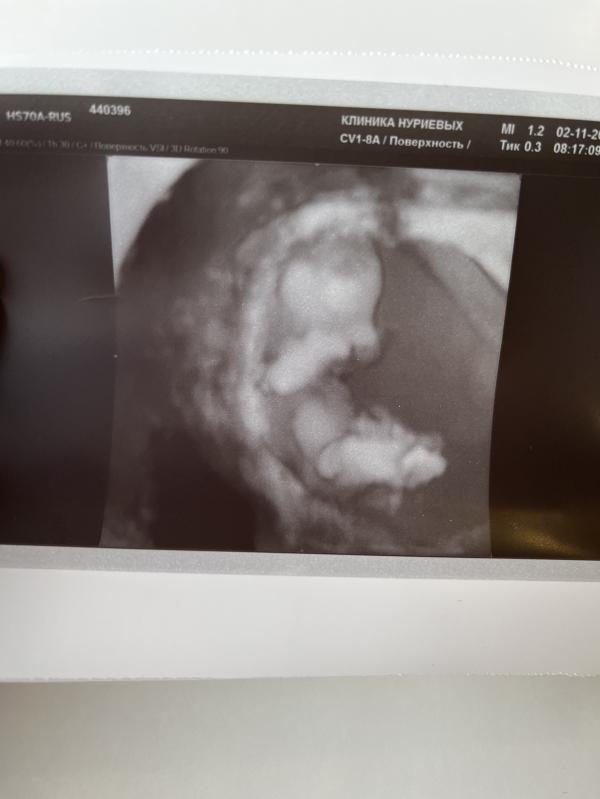

Мы прошли первый скрининг 🥳

Ктр 5,3 см - это единственное, что запомнила😅

ПДР- 17 мая 2023г🙏🏼 после майских шашлыков можно и рожать пойти😂

И самое главное - предположили мальчика 💙разумеется, это неточно, перед Новым годом узнаем точно, какой там у нас подарочек 🎁